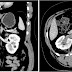

Observing the patient's symptoms, medical history and imaging remain the fundamental source for diagnosing RVT. Imaging is used to detect the presence of a blood clot. In an abnormal kidney with RVT, a blood clot is present in the renal vein. In cases where the renal vein is suddenly and/or fully blocked, the kidneys will enlarge, reaching its maximum size within a week. An ultrasound imaging can be used to observe and track the size of the kidneys in RVT patients. Ultrasound is not efficient for use in detecting blood flow in the renal veins and artery. Instead a color doppler ultrasound may be used to detect renal blood flow. It is most commonly used to detect RVT in patients who have undergone renal transplantation. CT angiography is currently the top choice in diagnosing RVT. It is non-invasive, relatively cheap and fast with high accuracy. CT scanning can be used to detect renal enlargement, renal tumors, blood flow and other renal pathologies. An alternative is magnetic resonance angiography or MRA. It is non-invasive, fast and avoids radiation (unlike a CT scan) but it is relatively expensive. MRA produces detailed images of the renal blood flow, vesicle walls, the kidneys and any surrounding tissue. An inferior venocavography with selective venography can be used to rule out the diagnoses of RVT.